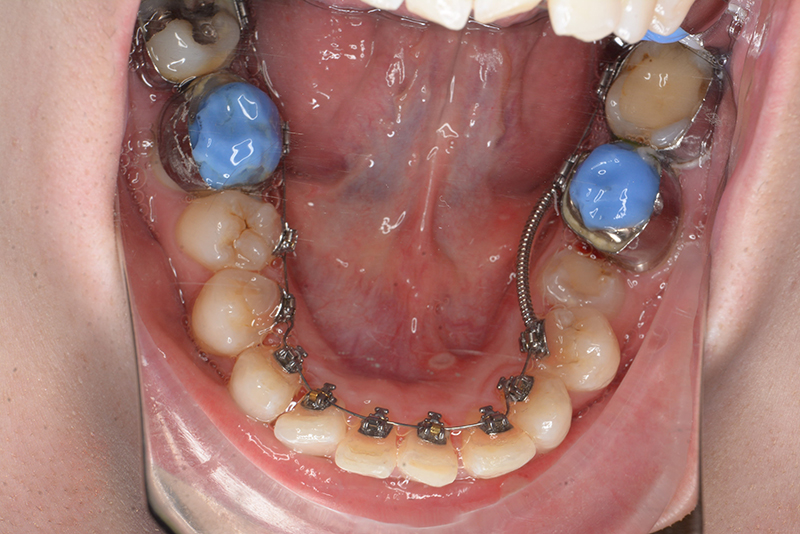

動的治療中のIOP(治療開始後12ヶ月)

動的治療中のIOP

(治療開始後12ヶ月)

IOP